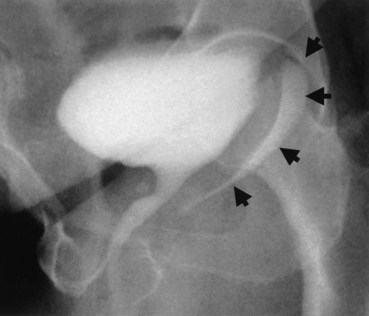

An endoscopic examination should be performed in patients with a suspicion of VVF (Fig. 77–5). Immature fistulae may appear as an area of localized bullous edema without distinct ostia. Mature fistulae may have smooth margins with variably sized ostia. In some cases, multiple pits and cavities along an area of the traumatized posterior bladder wall, in the setting of a small VVF, may make it difficult to identify the exact fistula tract. In these cases, a guidewire or ureteral catheter may be placed through the working channel of the cystoscope and into the fistula tract (Fig. 77–6). Visualization of the wire in the vagina confirms the exact location of the VVF on both the bladder and genital sides. Cystourethroscopy can confirm the presence of the fistula, but also may assess the size of the tract, the presence of collateral fistulae, and the location of the ureteral orifices in relation to the fistula. Small fistulae, usually less than 3 to 4 mm in diameter may be amenable to simple fulguration, which can be performed at the time of cystoscopy (see later discussion) (Stovsky et al, 1994). Importantly, in the setting of a prior history of pelvic malignancy, a biopsy of the fistula is often done to evaluate for the possibility of a recurrent malignancy. Fistulae located near or at the ureteral orifice may require ureteral reimplantation at the time of VVF repair. This type of requirement would usually mitigate against a completely transvaginal attempt at repair.

A cystogram and/or voiding cystourethrogram (VCUG) and an upper tract study should be performed in patients being evaluated for a VVF. The cystogram may objectively determine the presence and location of the fistula. Upon filling of the bladder, contrast often begins to opacify the vagina, almost immediately confirming the presence of a VVF. VVF are often best seen in the lateral projection (Fig. 77–7) in which the bladder and vagina are not superimposed. Often, the actual VVF tract may be visible in the lateral projection (Fig. 77–8). However, voiding images may be necessary in some patients with small fistulae, to demonstrate the VVF. The slight increase in intravesical pressure that accompanies micturition is usually adequate to demonstrate even very small fistulae. Importantly, a cystogram that fails to demonstrate a suspected VVF, but lacks voiding images or postvoid images, should be considered nondiagnostic. During voiding, care should be taken to exclude vaginal voiding or reflux of contrast from the introital region cephalad into the vagina, which would produce a falsely positive image. An involuntary bladder contraction can be provoked with rapid filling during cystography, and if the intravesical pressure rises sufficiently, this may also be sufficient to demonstrate a VVF when the filling images of the cystogram failed to demonstrate it. In some instances, a cystogram can also make an assessment of bladder capacity (important in the setting of prior radiotherapy), cystocele, bladder neck competence, and vesicoureteral reflux, any of which may have an impact on operative repair.